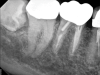

Fig 3. Case 1: Periapical imaging of the maxillary right (Fig 2) and mandibular right (Fig 3) quadrants initially showed no obvious pathology, aside from the horizontally impacted tooth No. 32. Secondary imaging following successful relief of pain after administration of an inferior alveolar nerve block revealed pre-eruptive intracoronal resorption in tooth No. 32 with resultant symptomatic irreversible pulpitis as the likely source of pain (Fig 4).

Figure 3

Although the patient's chief complaint was consistent with a degenerative pulpitis, the clinical and radiographic examination was initially unremarkable. All teeth in the maxillary and mandibular right quadrants were normally responsive to pulp sensitivity testing, and they were neither percussion nor palpation sensitive. Neither swelling nor sinus tracts were present, and the periodontal examination revealed normal probing depths and lack of mobility throughout the quadrant. Initial periapical radiographs revealed normal PDL spaces surrounding teeth Nos. 30 and 31, as well as a horizontally impacted No. 32 with a radiolucency within the crown in close proximity to the distal root surface of No. 31 (Figure 2 and Figure 3). Because the reported pain was severe, and in an effort to not only diagnose the issue but also offer some respite from the severe pain the patient was experiencing, an inferior alveolar nerve block was administered using 3.4 cc 0.5% bupivacaine with 1:200,000 epinephrine. Within 5 minutes of administration, the patient reported complete resolution of his pain.

Given the confirmation of a likely odontogenic source of pathology since pain was relieved by the block anesthesia, secondary periapical imaging was taken, which showed intracoronal resorption in the unerupted tooth No. 32 (Figure 4). Because of the visualizable pathology and signs and symptoms consistent with a symptomatic irreversible pulpitis, the patient was referred to an oral and maxillofacial surgeon for extraction of tooth No. 32. The patient reported complete resolution of symptoms following extraction of the affected tooth. Communication from the oral surgeon confirmed the diagnosis of intracoronal resorption on tooth No. 32.